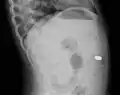

Airways

It is possible for a foreign body to enter the airways and cause choking.[5] A choking case can require the fast usage of basic anti-choking techniques to clear the airway.

In one study, peanuts were the most common obstruction.[6] In addition to peanuts, hot dogs, grapes, and latex balloons are also serious choking hazards in children that can result in death. A latex balloon will conform to the shape of the trachea, blocking the airway and making it difficult to expel with basic anti-choking techniques.[7]